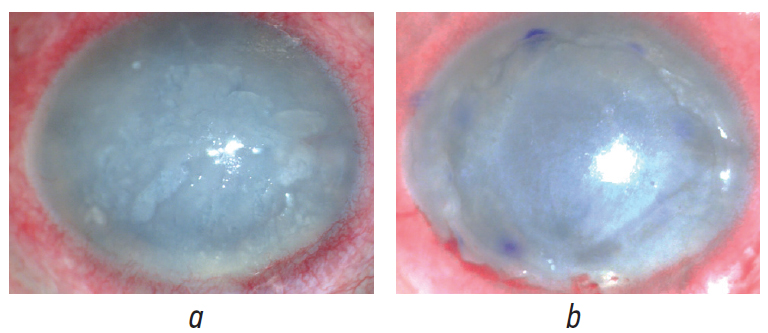

По данным ОКТ роговицы во всех случаях отмечалось наличие диффузного эпителиально-стромального отёка с элементами субэпителиальной фиброплазии и фиброзных изменений на уровне боуменовой и десцеметовой мембран различной степени выраженности (рис. 3).

Рис. 3. Оптическая когорентная томограмма роговицы: диффузный отёк эпителия и стромы роговицы, суб- и интраэпителиальные кистозные полости (буллы), субэпителиальная фиброплазия, фиброплазия на уровне боуменовой и десцеметовой мембраны: а — пациент М.; b — пациент К.

Fig. 3. The OCT of the cornea: diffuse edema of the corneal epithelium and stroma, sub- and intraepithelial cystic cavities (bullae), subepithelial fibroplasia, fibroplasia at the level of Bowman and Descemet’s membranes: a — patient M.; b — patient K.

По данным предоперационной ОКТ центральная толщина роговицы варьировала от 981 до 1960 мкм и в среднем составляла 1008 ± 96 мкм.

Критерием отбора для проведения задней послойной кератопластики с использованием фемтосекундного лазера стало отсутствие грубых рубцовых изменений стромы роговицы и новообразованных сосудов в оптической зоне, а также сохранение относительно равномерного профиля её передней и задней поверхности по данным предоперационной ОКТ.